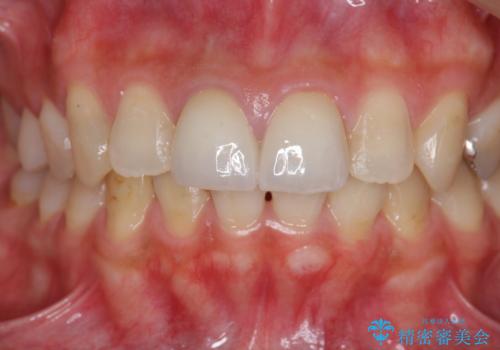

虫歯の徹底的な除去、根管治療を行いセラミック治療に入る前の環境をしっかりと整えたのち審美的なジルコニアセラミックで治療を仕上げました。